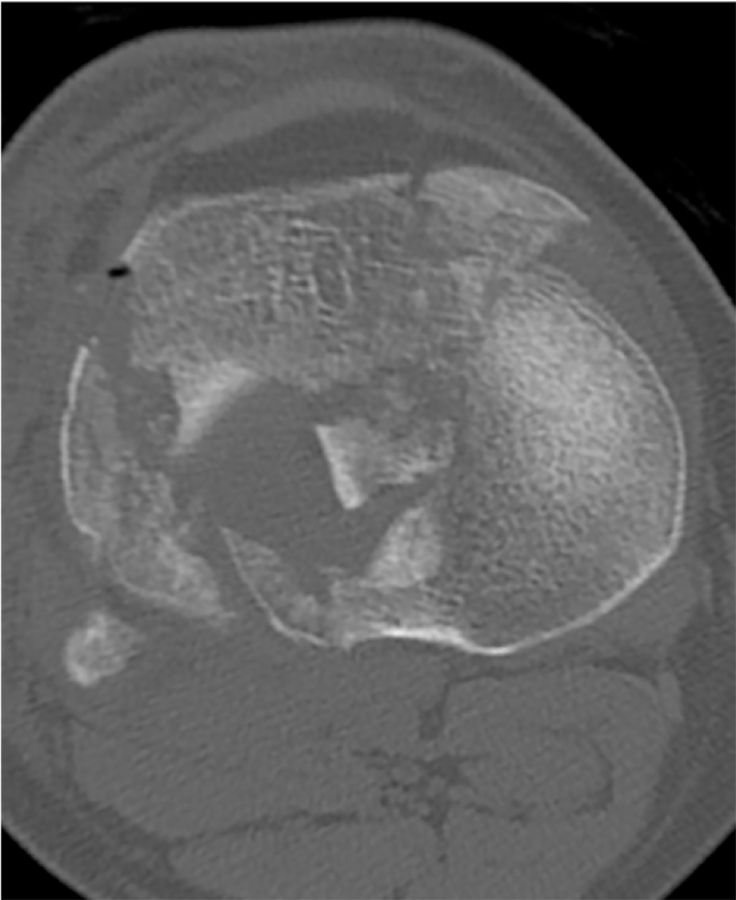

Exposure of the knee can be quite difficult especially if the stiffness is the result of bony impingement. I remember a few patients with intraarticular distal femur fractures that had healed in such a malposition that the resulting step off blocked the flexion of the knee (Figure 9a, b, c).

Dealing with this situation in a knee with less than 45 degrees of flexion requires a very careful step by step exposure. Usually I start by performing a medial capsular release to be able to externally rotate the tibia as far as possible. Once this allows flexion of the knee to 40 to 60 degrees distal resection of the femur can be attempted. Further flexion is achieved with a free hand cut of the proximal tibia to disengage the bony impingement. Despite opening up the extension gap it can be difficult to flex the knee and expose the tibia without a femoral peel and release of the MCL (Figure 10) to allow for separation of the femur from the tibia [6].